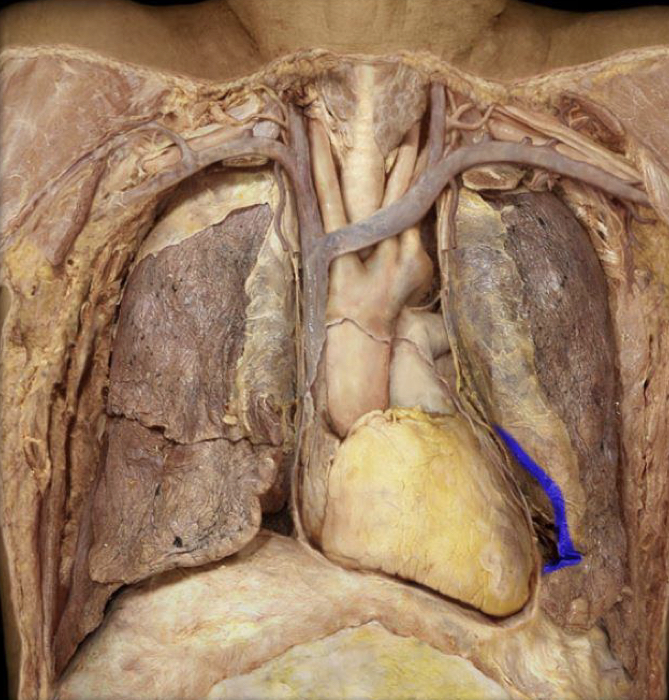

What structure is highlighted in blue?

Cardiac notch